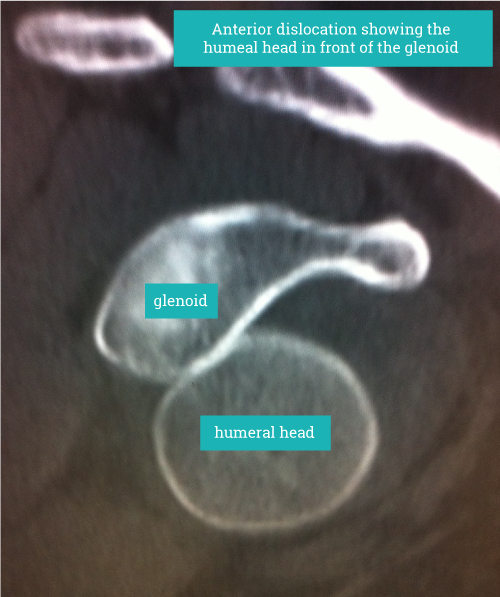

Diagnosis is based on clinical history and signs. Confirmation by an x-ray showing the dislocated shoulder can be helpful. Imaging such as MRI scanning will show the underlying structural problems such as a labral tear (soft tissue Bankart lesion), bony injuries such as glenoid rim fractures (bony Bankart lesion) and impaction fractures on the back of the humeral head (HillSachs lesion) where It has contacted the anterior glenoid during the dislocation. In older persons the risk of damaging the rotator cuff at the time of dislocation is increased and should be actively looked for as rotator cuff tears in these circumstances can be quite substantial.

“Diagnosis is based on clinical history and signs. Confirmation by an x-ray showing the dislocated shoulder can be helpful.”